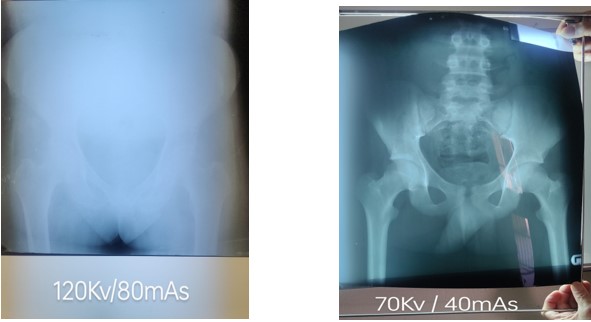

Original quality Much improved image using less than half the dose!